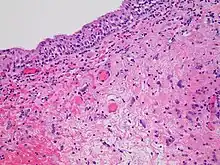

- Radiation necrosis

- Radiation necrosis is the death of healthy tissue near the irradiated site. It is a type of coagulative necrosis that occurs because the radiation directly or indirectly damages blood vessels in the area, which reduces the blood supply to the remaining healthy tissue, causing it to die by ischemia, similar to what happens in an ischemic stroke.[46] Because it is an indirect effect of the treatment, it occurs months to decades after radiation exposure.[46] Radiation necrosis most commonly presents as osteoradionecrosis, vaginal radionecrosis, soft tissue radionecrosis, or laryngeal radionecrosis.[5]